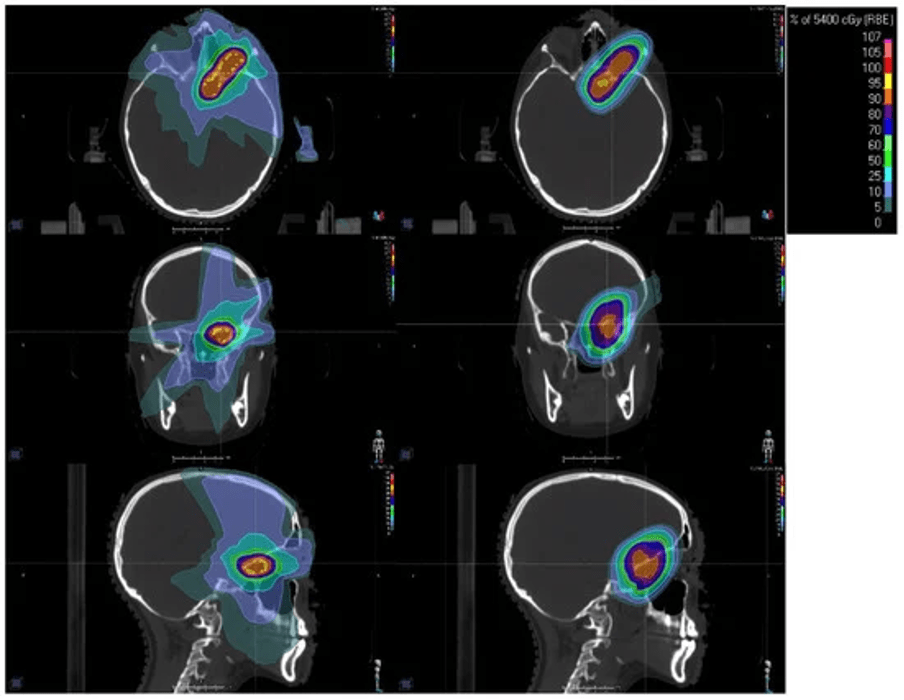

Conventional RT with photons, which is widely available around the world, has its peak dose at a shallow depth within the patient, with subsequent attenuation of the beam as it travels through tissue, tumor, and exits the body. Proton beams exhibit a Bragg peak phenomenon, in which energy loss peaks sharply within the tumor before the particle rests, with rapid dose falloff beyond this point. This enables more conformal dose distributions with a reduced dose to the surrounding healthy tissues (Figure 1). Consequently, PBT can lower the risk of acute and long-term side effects compared to conventional photon RT without compromising disease control.

Figure 1. Example radiation dose distributions for a 17-year-old female with an optic pathway glioma. Left column shows a photon intensity-modulated radiotherapy (IMRT) distribution with non-co-planar beams. The right column shows a pencil beam scanning proton beam therapy (PBT) distribution. Isodose line color legend is shown in the top-right inset. The axial, coronal, and sagittal views are shown in the top, middle, and bottom rows, respectively.